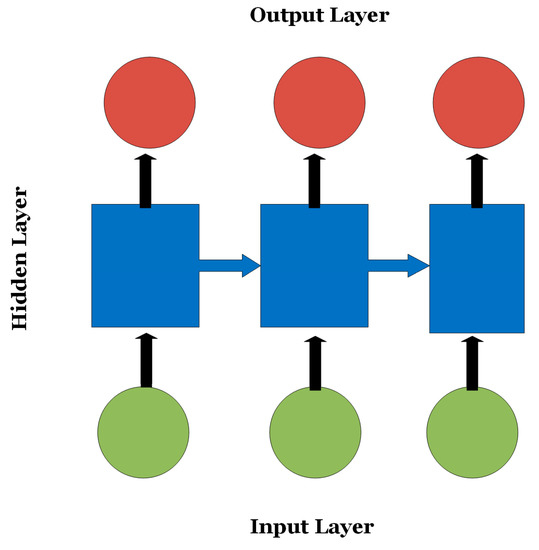

RNNs are variations of CNNs and ANNs that are beneficial in analyzing sequential or time-series data such as EEGs and genomic sequences [12]. RNNs are composed of several CNN/ANN units where the decision of a certain unit depends on the internal state of a previous unit offering a “short memory” feature of the data context as shown in Figure 3. Since exploding or vanishing gradients may occur during the training process of RNNs, LSTMs were introduced to keep track of long-term dependencies among sequential data and address the exploding and vanishing gradients dilemma.

Figure 3.

An RNN where the decision of the nodes in the output layer depends on the internal state of the hidden nodes.